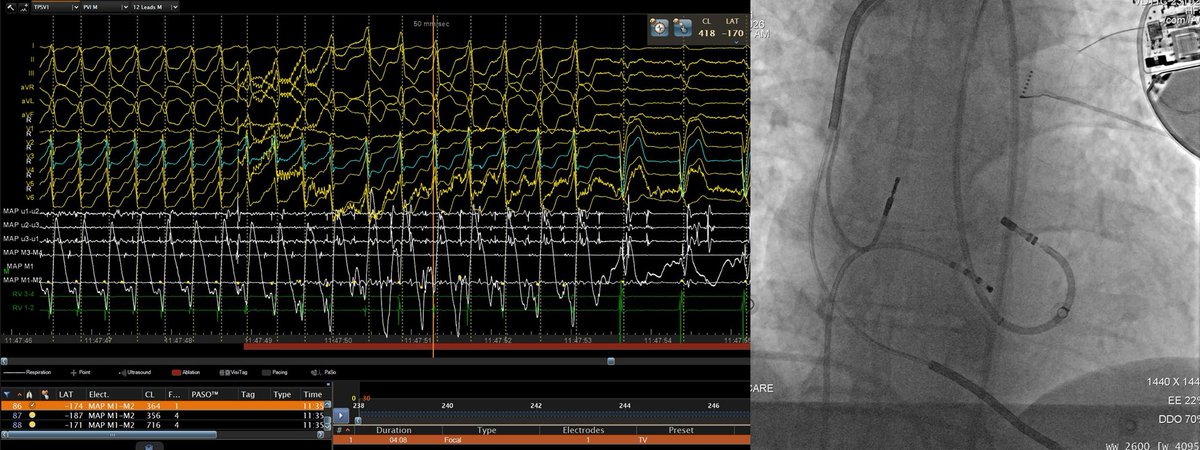

Celebrating 1yr since the publication of our Atlas of ConductSystemPacing #LBBAP #HBP! Thanks @ilpensiero for their support & to the readers for their trust! I hope it has been (& will be) useful to become confident in recognizing #CSP in your procedures! tinyurl.com/CSPAtlas